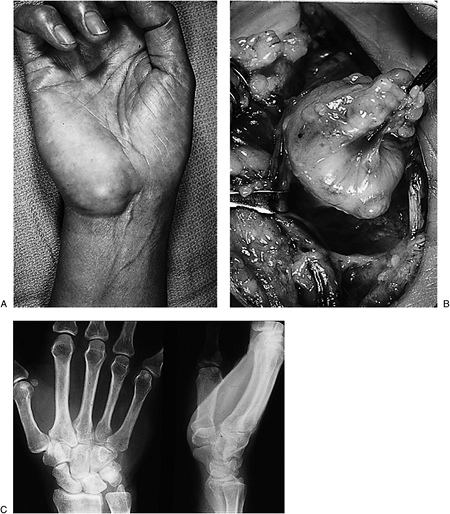

|

Figure 3-12 (A) This compound giant cell tumor of the tendon sheath presented as a palmar hand lesion (arrow). (B) It also presented as dorsally. (C) It was associated with several vital structures in the palm, and invaded the metacarpophalangeal joint of the middle finger. (D)

The characteristic histologic features of giant cells in a cellular matrix with scattered hemosiderin deposits are noted. (Hematoxylin and eosin, original magnification × 160.) |